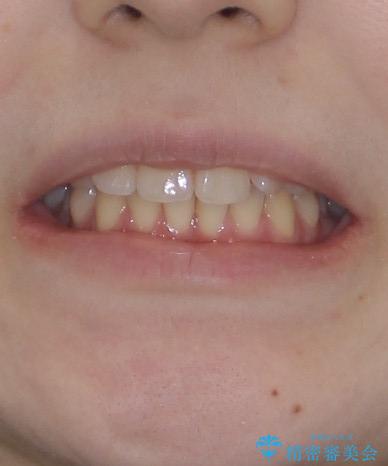

- 左上の前歯が出ていることを主訴として来院された患者様です。

当初はインビザラインを希望されていましたが、職業柄お茶する機会が多く装着時間を確保することが難しいとのことで、相談の上ワイヤー矯正の中では目立ちにくい審美装置で矯正を進めていくこととしました。

1年と少しで矯正治療を終えることができ患者様は大変満足されました。